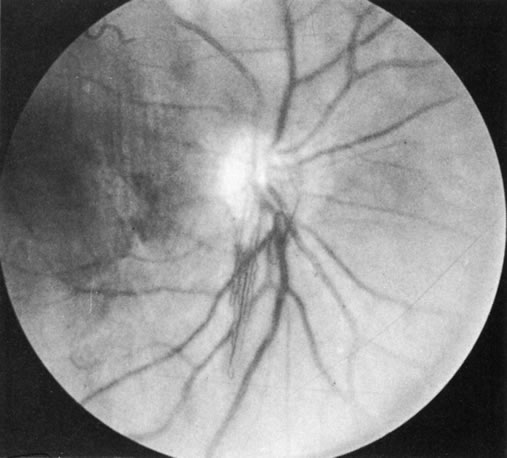

The Vogt-Koyanagi-Harada syndrome (VKHS) is a chronic, bilateral, exudative uveitis associated with whitening of the hair and eyelashes (Fig. 8), vitiligo, and meningeal irritation. It is a combination of two overlapping disease entities. VKHS is a severe anterior-segment inflammation associated with dysacousia, vitiligo, alopecia, and poliosis. Harada's disease is limited largely to posterior uveal inflammation with serous retinal detachments, disc involvement, meningeal inflammation, and sometimes skin and hair changes (Figs. 9 and 10). Because the symptoms of the two diseases overlap significantly and their histopathologic features are similar, the two are now regarded as a single disease entity.

Fig. 9. Optic nerve involvement in Vogt-Koyanagi-Harada syndrome. (Courtesy of Dr. R. Weinberg.)

Fig. 10. Posterior involvement in Vogt-Koyanagi-Harada syndrome with pigmentary changes and scarring. (Courtesy of Dr. R. Weinberg.)